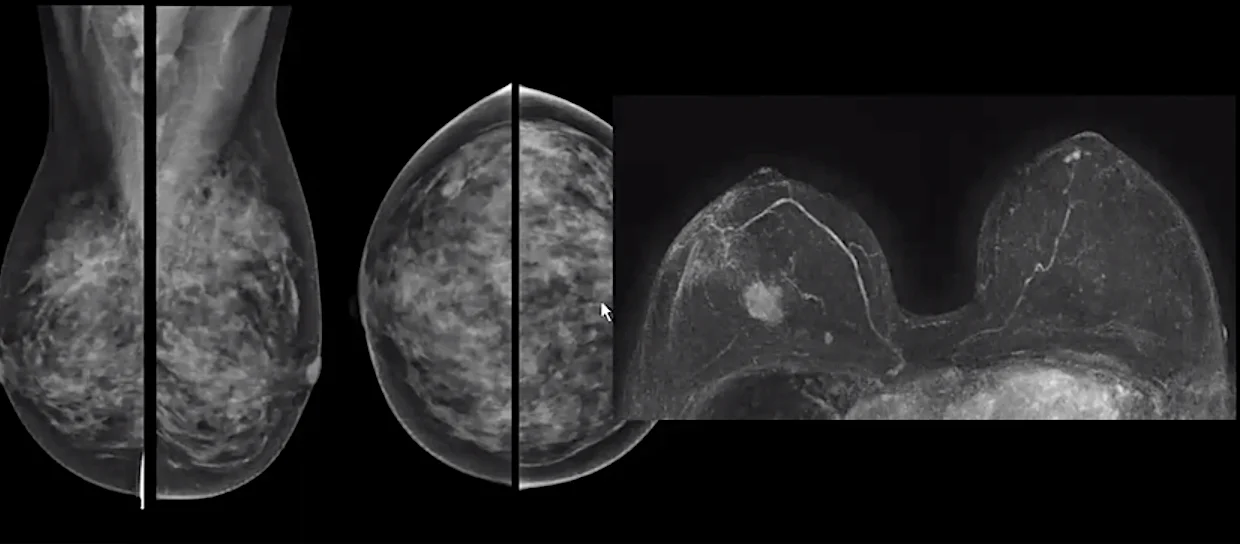

In areas where mammography is less accessible, clinical breast examination by trained professionals provides an important safeguard, particularly in detecting palpable lesions. Those at high genetic risk, including BRCA mutation carriers, may require earlier and more intensive surveillance with modalities such as MRI or ultrasound, and some evidence suggests that high-risk men also benefit from regular screening. Most importantly, when any abnormality is found, rapid access to diagnostic work-up, including biopsy, imaging, and multidisciplinary evaluation, is essential to avoid delays that can turn a treatable cancer into an advanced, life-threatening disease.

Abbreviated Breast MRI.